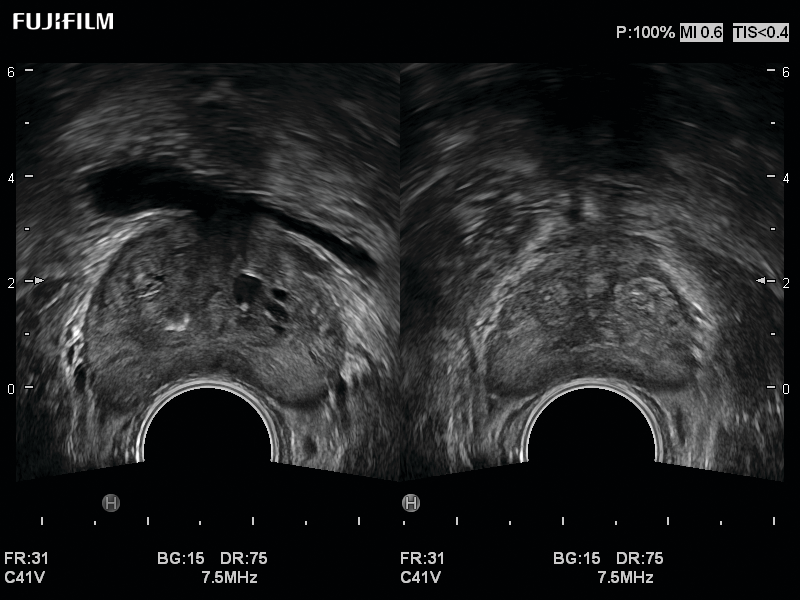

Exclusive 200° field of view end-fire prostate biopsy transducer. Allows visualization of the entire gland from apex to base.

Side-Fire Bi-Plane prostate transducer with simulataneous display and wide scanning, as well as a 200° field of view.